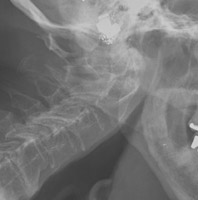

- Click on the image for a larger versionALateral view of the cervical spine. The patient is severely osteopenic. Nevertheless, there is irregularity of the neural arches at the C1 level.